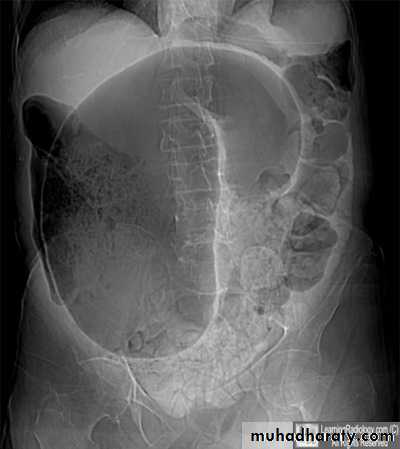

Sigmoid volvulus

Inverted U-shaped appearance of distended sigmoid loopLargest and most dilated loops of bowel are seen with volvulus

Loss of haustra

Coffee-bean sign à midline crease corresponding to mesenteric root in a greatly distended sigmoid

Sigmoid volvulus – bowel loop points to RUQ

Cecal volvulus – bowel loop points to LUQ